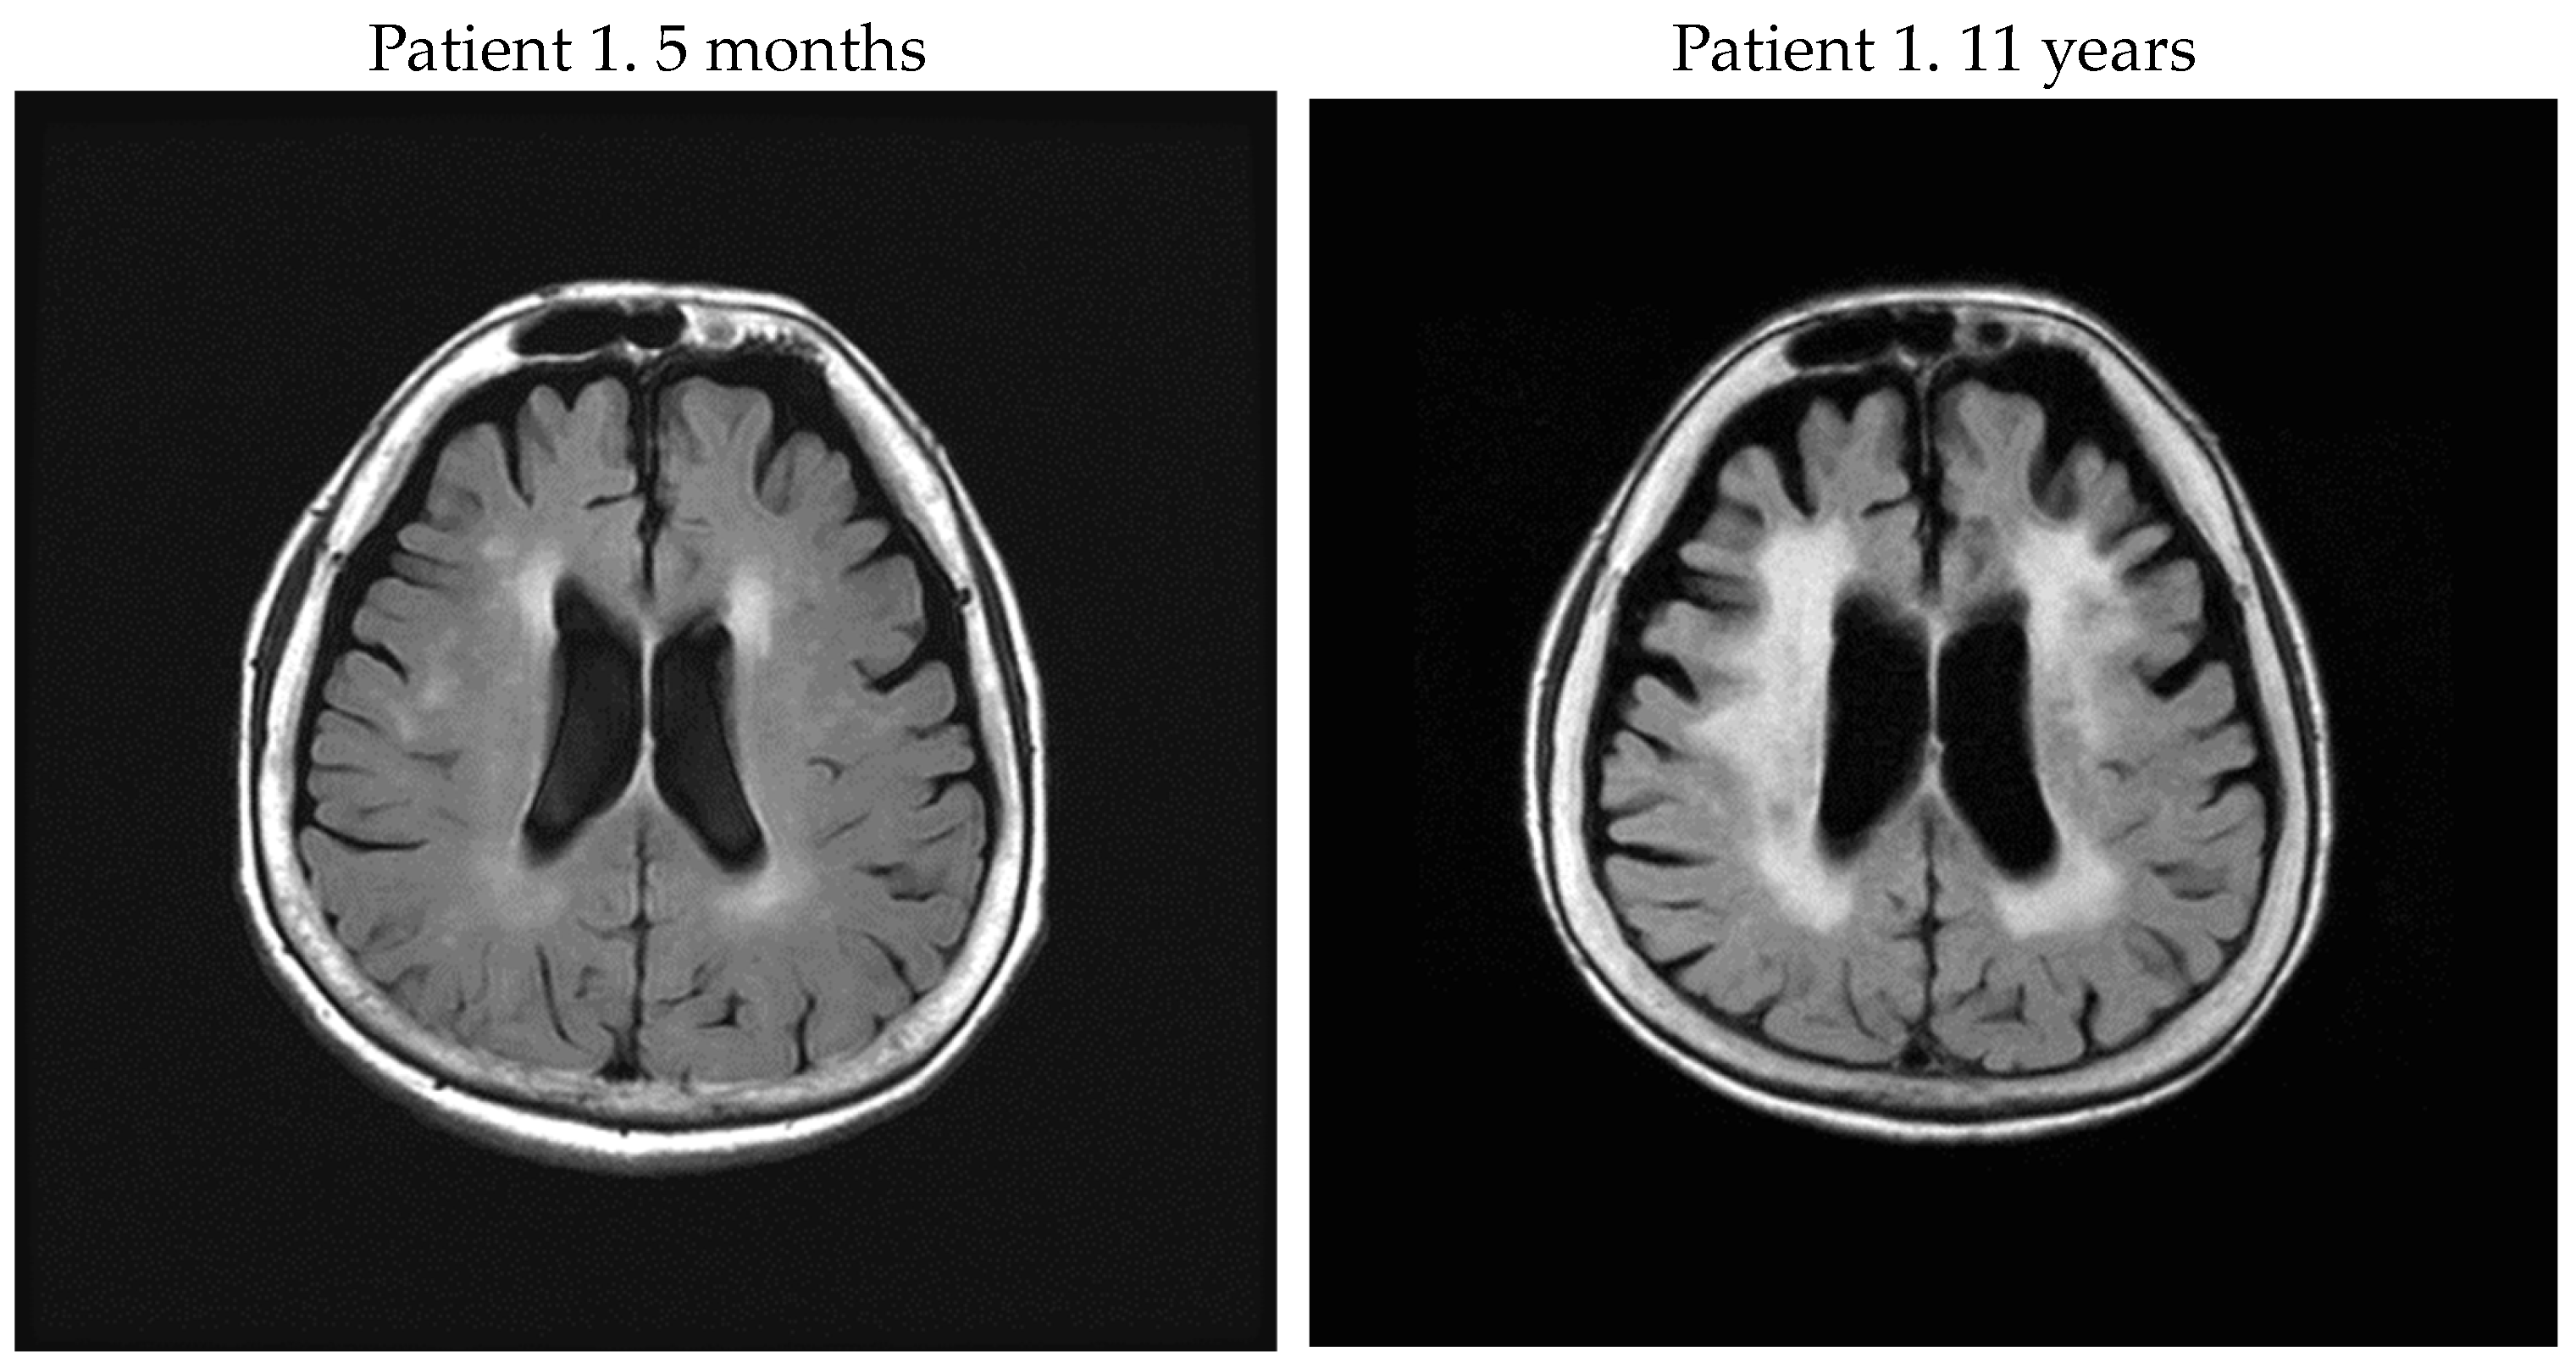

| 1 | F | 71 | 71 | 5 m | rapid | 1 | 1 | — | 2048 | 26,772.2 | 63 | no | 9 |

| 81 | 11 y | 3 | 3 | 14.98 | — | — | — | yes | 10 | ||||

| 2 | F | 61 | 61 | 3 m | rapid | 2 | 2 | — | 2048 | 14,492.8 | 70 | no | 7 |

| 67 | 7 y | 3 | 3 | 3.89 | 1024 | 5083.7 | 43 | yes | 6 | ||||

| 4 | F | 65 | 78 | 13 y | rapid | 3 | 3 | 18.69 | 2048 | 7065.4 | 51 | yes | 5 |